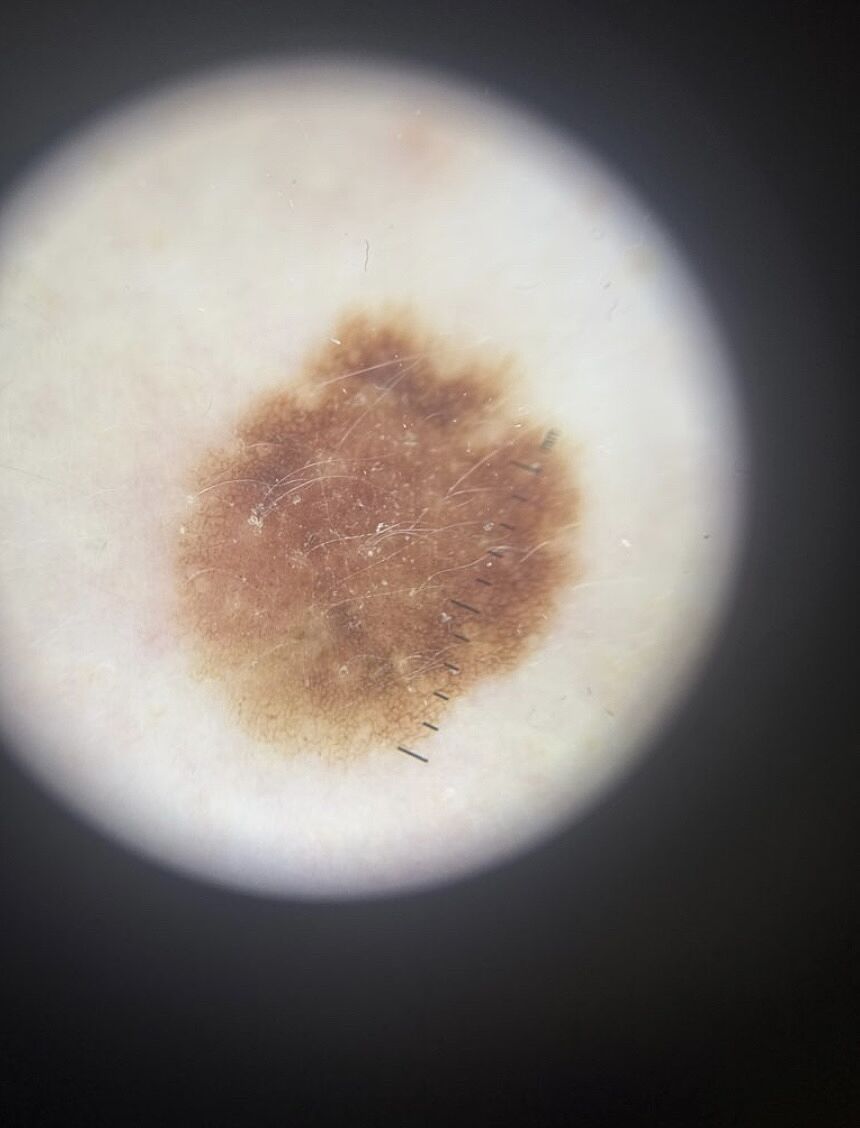

Була в лікарки, родимку спостерігаю в неї рік. Ця родимка в мене з дитинства. Коли прийшла до неї перший раз вона сказала що вона неправильна і є трохи темні вкрапленя. За рік приходила до неї два рази все було ок. Сьогодні прийшла і вона каже що родимка не змінена вони фотографують її але вона не подобається її і вона сумнівається. Радить біопсію. Я дуже налякана. Сказала її може подивимся ще 3 місяці. Вона каже добре. Я не хочу біопсії якщо видаляти то з відступом. Але ще сумніваюся. Хочу почути думки. І чи є наші лікарі які дають консультацію онлайн.

На фото обычная родинка

Можете онлайн.но на фото родинка и родинка.Вы б мою увидели и в обморок упали бы))

Дай Бог. Ця родимка має в мене трохи зубчастий край памятаю з дитинства і за темні місця здається були теж я звертала увагу. Але немаю давніх фото моніторю тільки рік.

Лікарка каже що її смущає край і темні вкрапленя.

У меня визуально похожая 2 фото , удалила и забыла